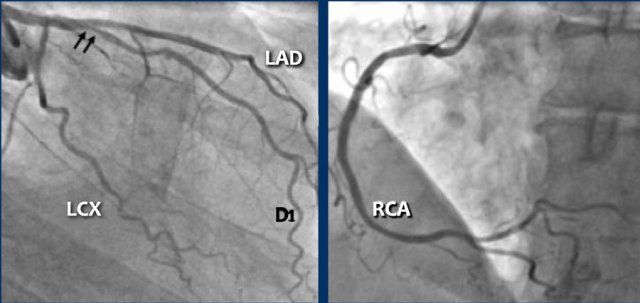

Continue with the next images...

A: ICA correlates with CTA and shows an 80% stenosis in the mid LAD (white arrows) and a 60% stenosis in the D2 branch (black arrows). The D2 stenosis was overestimated on CTA.

B: PCI was performed during which a drug eluting stent (DES) was implanted with good results (white arrows).

Same patient.

A: Curved MPR of the LAD with non-calcified plaque causing moderate (50-69%) stenosis.

B: The so-called “spider-view” (LAO caudal) of the heart with a 70% stenosis in the proximal LAD. Note the presence of SA nodal artery arising from the proximal LCX and coursing to posterior direction.

C: A drug eluting stent (DES) was implanted into the proximal LAD with good results.